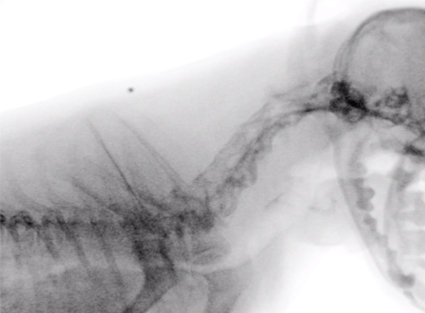

Radiología para Mascotas Exóticas

- Aves

- Reptiles

- Roedores

- Pequeños mamíferos